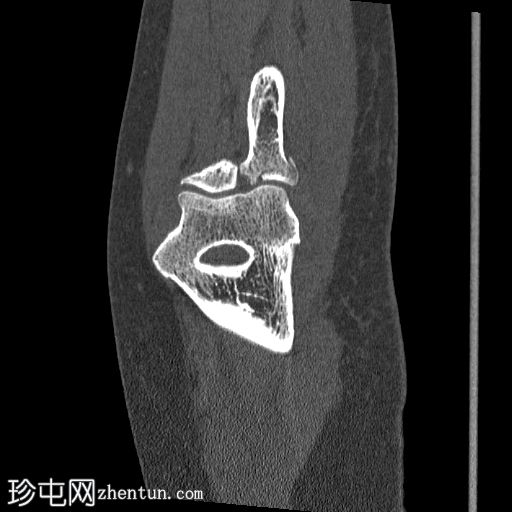

矢状面骨窗

显示整个桡骨头粉碎性骨折,特征为两个以上大骨折块,以及倾斜且受压的关节节。

这表明该骨折为不稳定骨折,根据Mason桡骨头骨折分型,为IIIC型。

远端肱骨和可见尺骨未见骨折征象。

此外,由于关节积血导致关节扩张,肘关节脂肪平面弯曲。